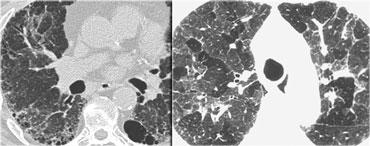

Đây là một trường hợp sarcoidosis phế nang.

Hãy cuộn qua các hình ảnh.

Hình ảnh trông giống như tăng tỷ trọng dạng kính mờ, nhưng khi quan sát kỹ hơn có thể nhận thấy rằng sự tăng tỷ trọng này là kết quả của nhiều nốt nhỏ tập hợp lại.

Cũng lưu ý hạch to rốn phổi.

Sarcoidosis phế nang (2)

Bên trái là bệnh nhân nữ 47 tuổi với triệu chứng ho khan, khó thở nhẹ và xét nghiệm máu bình thường.

Bệnh nhân được chụp X-quang ngực và điều trị kháng sinh.

Phim kiểm tra được chụp lại do bệnh nhân không cải thiện.

Phim X-quang ngực đầu tiên cho thấy đông đặc hai bên ở thùy dưới (mũi tên), ban đầu được diễn giải là nhiễm trùng.

Sau hai tuần điều trị kháng sinh, không có cải thiện.

Chẩn đoán phân biệt lúc này bao gồm u ác tính (ung thư phế quản phế nang hoặc u lympho), viêm phổi tăng bạch cầu ái toan, viêm phổi tổ chức hóa, bệnh Wegener hoặc một thể không điển hình của sarcoidosis.

Tiếp tục với hình ảnh HRCT.

Hãy cuộn qua các hình ảnh bên trái.

Có nhiều vùng đông đặc.

Các dấu hiệu kèm theo bao gồm hạch to rốn phổi và trung thất.

Chẩn đoán phân biệt trên hình ảnh CT về cơ bản giống như trên X-quang ngực.

Kết quả mô bệnh học xác nhận sarcoidosis phế nang.

Chỉ có một gợi ý duy nhất cho chẩn đoán, đó là sự hiện diện của các nốt nhỏ có thể nhận thấy ở hình 3, nhưng rất khó quan sát.

Trường hợp này minh họa rõ ràng rằng sarcoidosis thực sự là “kẻ bắt chước vĩ đại”.

Do đó, sarcoidosis cần được đưa vào danh sách chẩn đoán phân biệt của chúng ta!